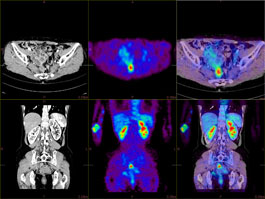

The PET/CT Fusion protocol provides flexible and simple image overlay analysis. Standard Uptake Value calculations are enabled with ROIs and VOIs.